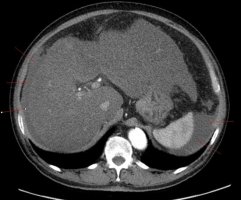

급성 췌장염은 췌장의 염증성 병변과 장기간 정상적인 췌장 기능의 손상을 나타내는 질환으로, 췌장염은 자가면역계에 의해 발생하는 경우가 많다. 염증의 원인에 따라 다양한 형태로 발생할 수 있으며 급성 췌장염의 경우 췌장에 갑작스러운 염증이 발생합니다. 급성 췌장염은 다양한 원인이 있으며 일반적으로 감염, 면역 장애, 약물 또는 식중독 등에 의해 발생합니다. 급성 췌장염의 증상은 경우에 따라 다양하며 일반적으로 복통, 구토, 변비, 피로, 식욕 부진, 발열, 무기력 등이 있습니다. 이러한 증상이 나타나면 즉시 의사를 만나 진단을 받아야 합니다. 의사는 병력, 신체 검사, 변비 및 복통의 정도, 식도 검사, 췌장 기능 검사 및 췌장 초음파를 통해 급성 췌장염을 진단할 수 있습니다. 의사는 또한 신체 검사 결과를 사용하여 염증의 원인을 확인하고 적절한 치료를 시작할 수 있습니다. 적절한 치료는 염증을 줄이고 회복 속도를 높이는 데 도움이 될 수 있습니다.